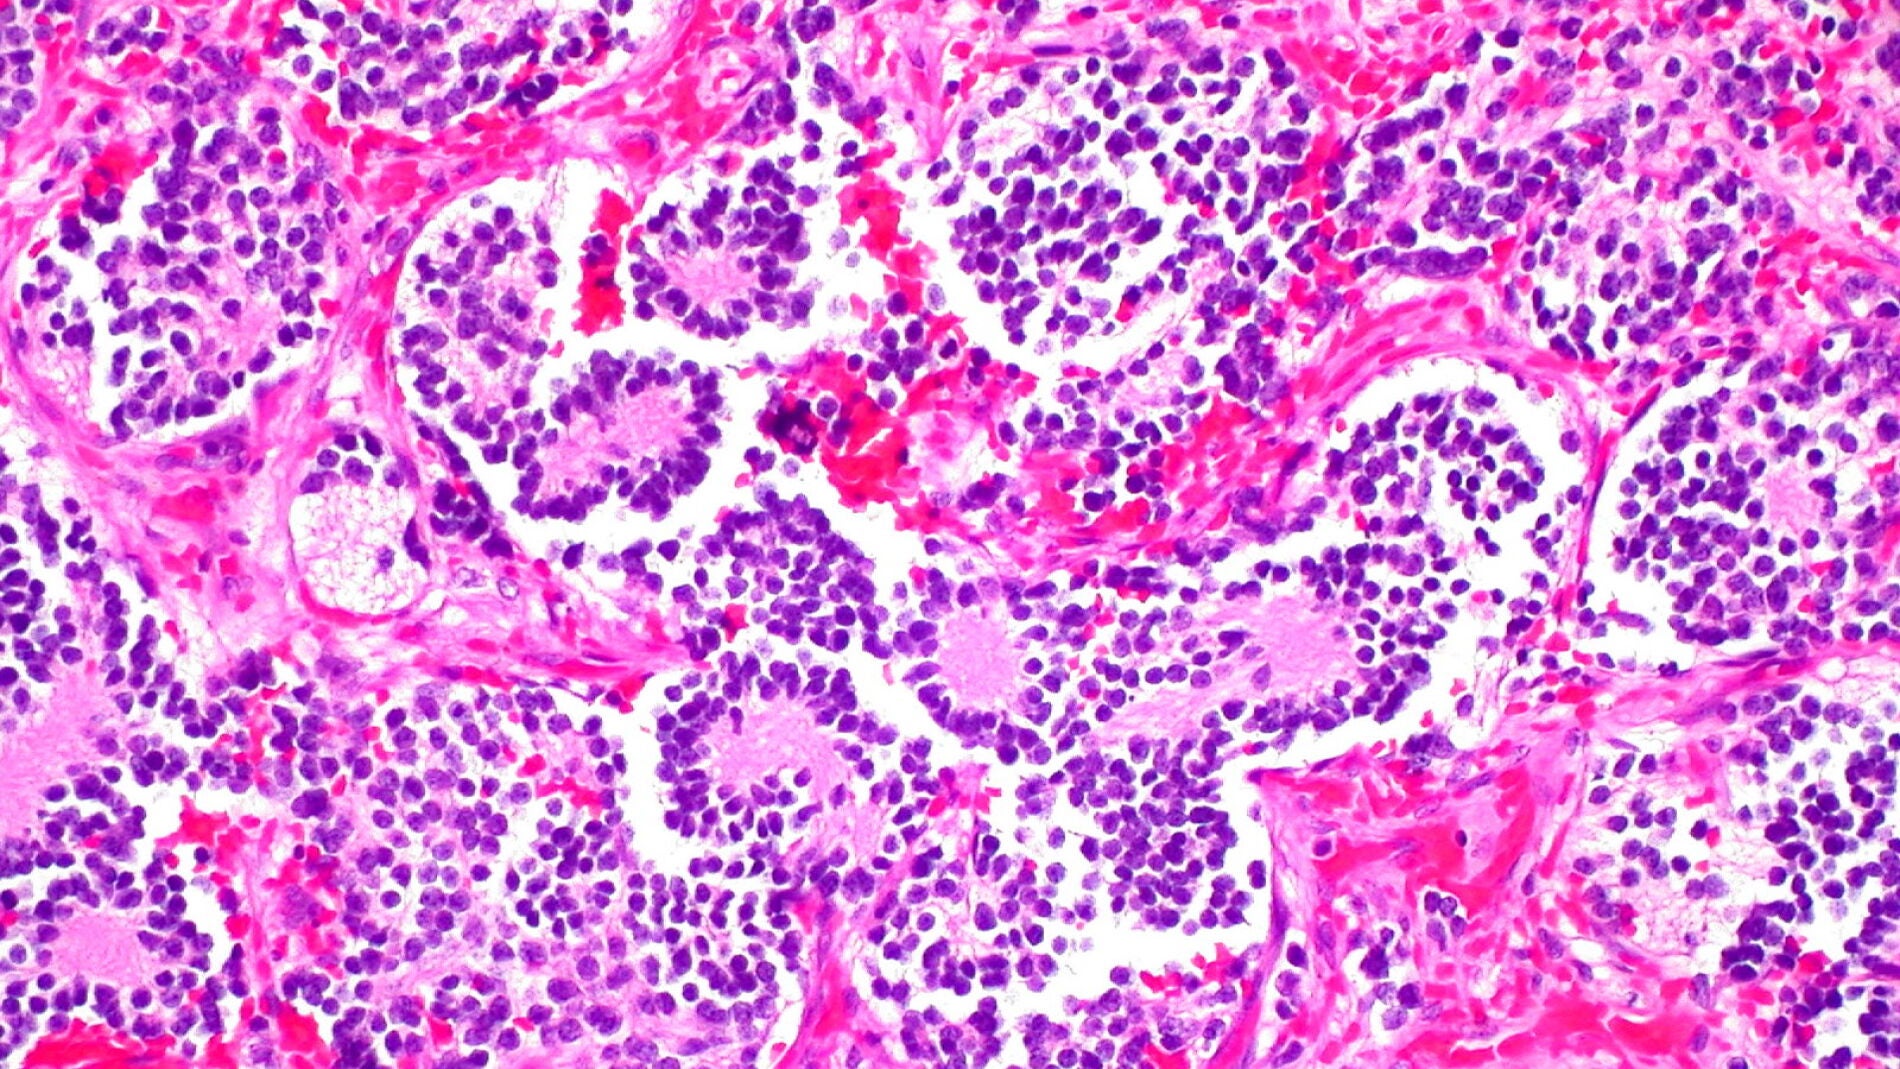

El neuroblastoma es un tipo de cáncer que se inicia en las células llamadas neuroblastos, un tipo de células nerviosas inmaduras que se encuentran en diferentes órganos del cuerpo.

Los neuroblastos no son malos ni tienen un destino tumoral inequívoco. De hecho, son imprescindibles en la vida. Durante nuestro desarrollo embrionario, los neuroblastos proliferan y migran, dando origen al sistema nervioso central y periférico. Solo cuando se reproducen de forma incontrolada, es cuando pueden generar tumores como el neuroblastoma.